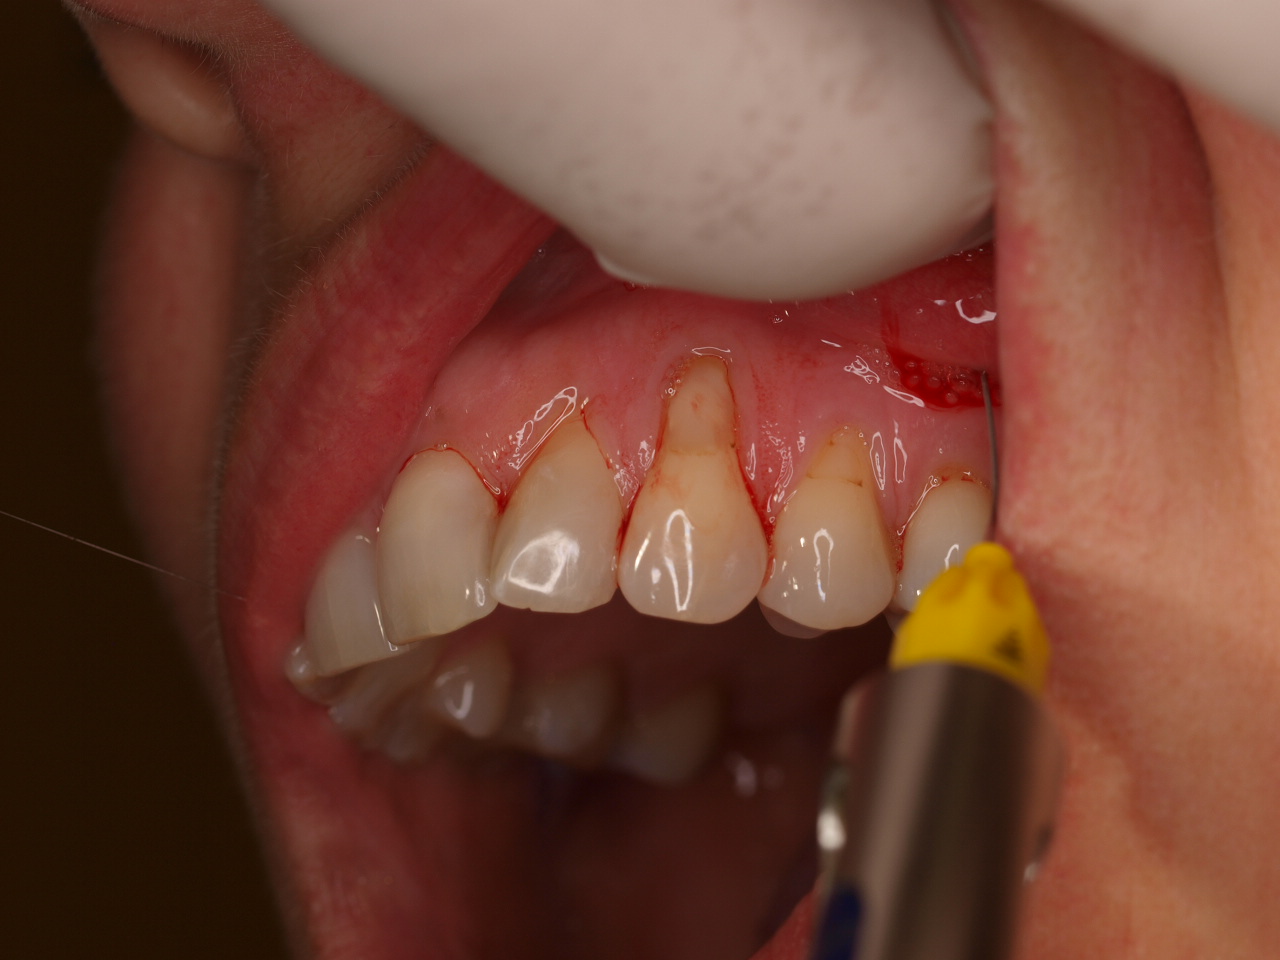

Multiple gingival recessions treated by MCAT with mucoderm® and Straumann® Emdogain® (2) - Rathe

Pre-operative clinical situation. Shallow multiple adjacent gingival recessions in the first quadrant.